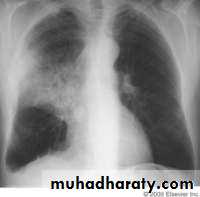

Pulmonary TB occurs in the lungs85% of all TB cases are pulmonary

chest radiographs that do not reveal any abnormalities or signs of healed TB disease

Initially infection with M involve middle &lower lung field &the focus is usually single .cell mediated immunity develops in the healthy person controlling the infection &cause the patient to remain asymptomatic .